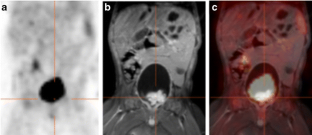

Fig. 1

Fig. 2

Fig. 3

Fig. 4

Fig. 5